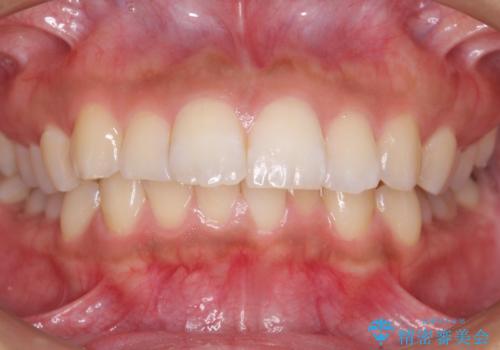

Eラインを整える治療 前歯を引っ込めます

- 前歯を下げたいと来院。

初めは、上だけ抜歯しましたが、もう少し口元を下げたいとのことで追加で下顎を抜歯しました。

年齢の割に歯が動きにくかったこともあり、また、追加で抜歯して結果として時間がかかってしまいました。口元が大きく下がり、結果には満足していただけました。

横顔が大きく変わり、満足していただけました。